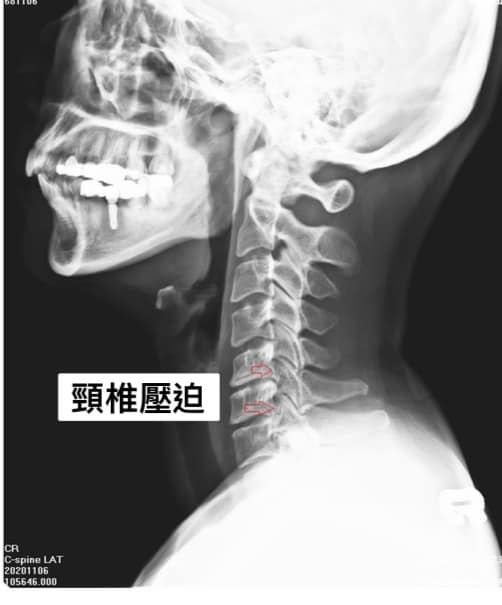

Cervical Spine Treatment Cases 頸椎治療案例 頸椎過直會導致肩膀酸痛嗎?中醫微創針刀療法成功改善頸椎弧度 2021.11.03 頸椎骨刺導致步態不穩、半身麻痛,一定要開刀嗎?中醫針刀治療100天改善實例公開 2021.10.07 冷水刺痛全身、下肢異常竟源自頸椎壓迫?MRI對比揭示非手術療法改善實證 2021.10.08 伏地挺身突然做不到?竟是C6C7頸椎壓迫導致神經肌力減退!中醫微創療法10週改善 2021.09.11 低頭族小心!頸椎滑脫竟導致長期頭痛肩痛與睡眠障礙|12次中醫微創治療成功矯正滑脫 2021.07.16 醫案實證:術後再發的脊髓壓迫症也能靠中醫療法改善 2021.07.10 手術後腳還是麻?頸椎開刀半年症狀未解,靠中醫微創8次改善右腳無力與手麻! 2021.06.30 狂送急診四次竟查不出病因!胸悶心悸原來是頸椎壓迫,靠針刀微創13次改善 2021.06.09 後縱韌帶鈣化壓迫脊髓!步態不穩、手腳麻木竟可逆轉?14週22次針刀治療真實見證 2021.05.06 什麼是中樞型脊髓型頸椎病?症狀、診斷與治療全解析 2021.05.28 神經根型頸椎病症狀解析:肩麻、手痛與肌肉萎縮 2021.04.16 嚴重心悸胸悶竟是頸椎問題!交感神經型頸椎病針治2次症狀明顯改善|真實病例與患者疼... 2021.04.07 從心悸胸悶到手麻夜痛難眠,她竟是頸椎壓迫!真實MRI對比見證中醫逆轉勝療效 2021.04.04 從手腳無力到步態不穩,他竟是頸椎脊髓型壓迫!三個月密集針刀療法逆轉勝|台北蔡大哥... 2021.03.31 頸椎椎間盤突出要一次動四節嗎?手術vs.保守治療完整解析 2021.03.27 ← 上一頁 2 3 4 5 6 下一頁 →